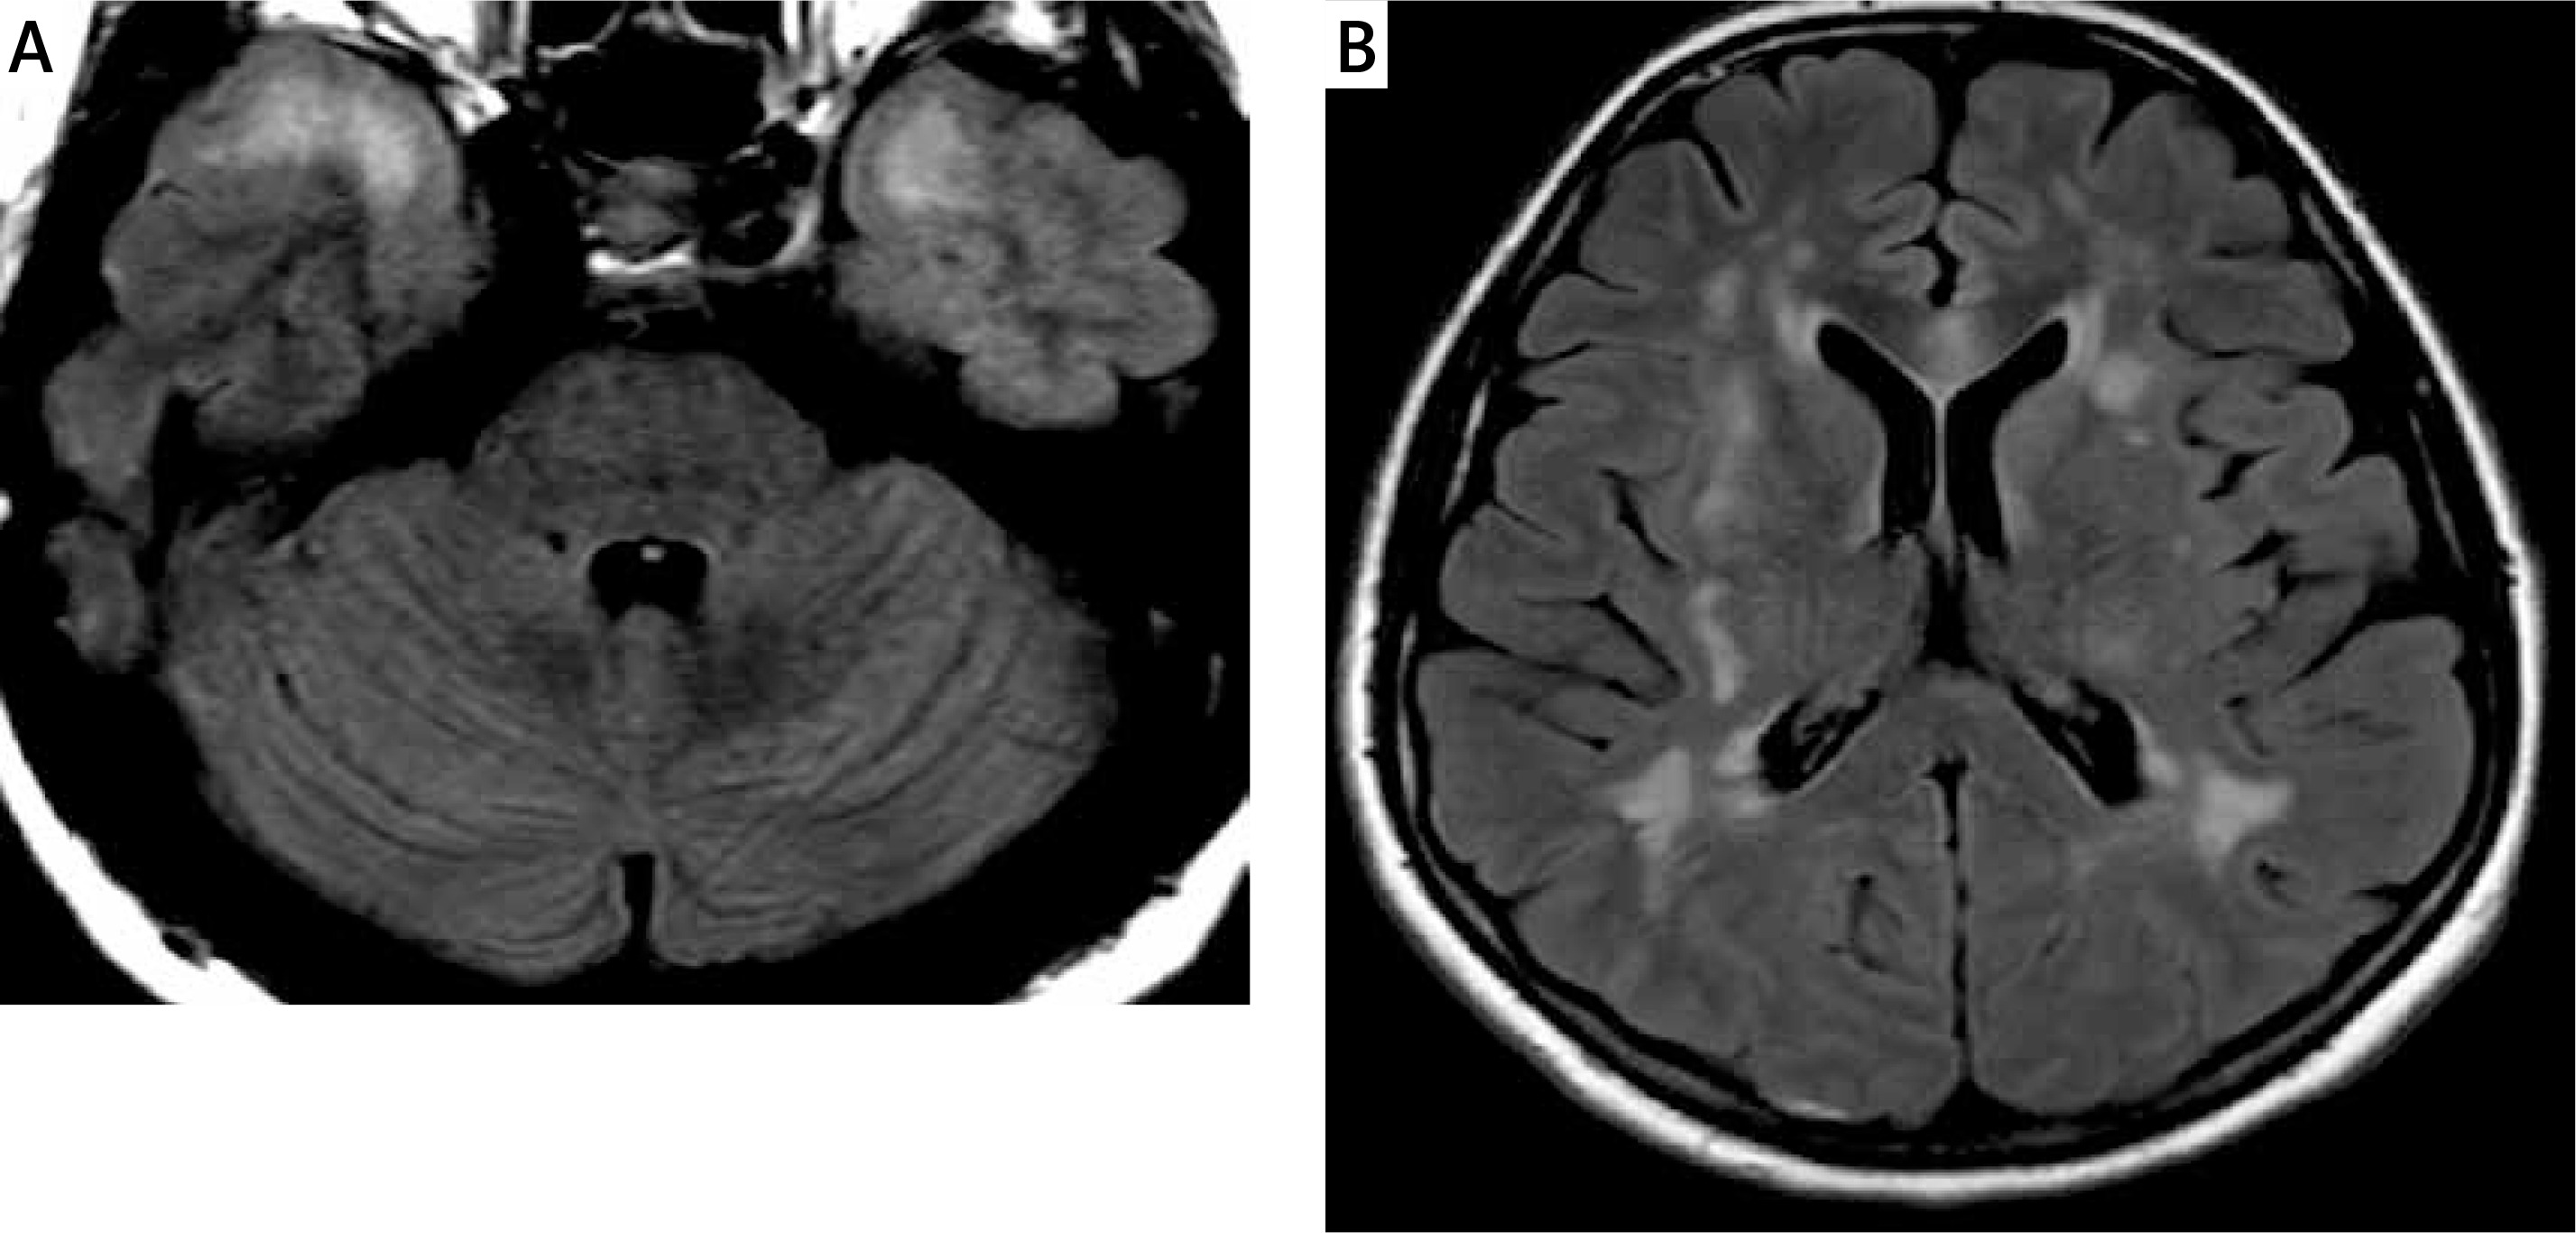

Figure 2

FLAIR image (A) shows confluent hyperintensities within the white matter of the anterior temporal poles. FLAIR image at the level of lateral ventricles (B) demonstrates white matter changes within the external capsules (mainly on the right)

Subsequent control MRI scans of the brain (13.08, 20.08.2020) showed white matter changes within the cerebral hemispheres without significant dynamics, i.e., the location and morphology. The sizes of the lesions were of similar volume with slight contrast enhancement (Figure 2).

One of the essential features of the white matter lesions’ radiological assessment is the analysis of their distribution and evolution over time. Some studies have suggested that both anterior temporal lobe involvement and external capsule involvement are characteristic markers that may differentiate CADASIL from other diseases [62–64].

In the present case, there were confluent white matter changes in the anterior temporal lobes and in the area of both external capsules (Figure 2). Similar localization of the lesions was described in another case recently reported by Zhang [49]. Some authors also emphasize the frequent location of the radiological changes in the upper frontal gyri, which is not present in our patient [64]. Other locations in which changes in the course of CADASIL syndrome may occur include the posterior temporal and occipital white matter, the basal ganglia, thalamus, internal capsule and the pons [64]. The involvement of the corpus callosum is a typical multiple sclerosis (MS) feature, could be present in ADEM and affects about 40% of patients with CADASIL [72]. The involvement of the corpus callosum is present in our case (Figure 5), but it was absent in the report of Zhang. In contrast, the occurrence of lesions in all infratentorial regions except the pons is unusual [49, 64, 72].